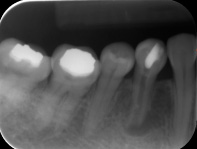

The procedure itself can be done in one visit or several sittings. It is routinely done with the placement of a rubber cloth so that the tooth can be isolated. Several exposures for radiographs are required before, after and during and after the procedures to ensure that it is performed in accordance to standards.

Aberration of the tooth resulting in higher chance of procedural complications. To name a few: it can be calcification of the root canal space making root canal treatment challenging, very curved canals causing higher chance of instrument fracture, premature tooth or tooth with limited tooth structure that that may fracture during treatment. (Radiographs) When such complications occur, the success rate may be affected and other follow-up treatment may be required.

- Persistent or recurrent root canal infection. This may occur even when a good root canal treatment has been performed. The assessment of re-treatment will be based on the quality of the root canal filling, the status of the disease and the nature of the signs and symptoms. (Radiographs)